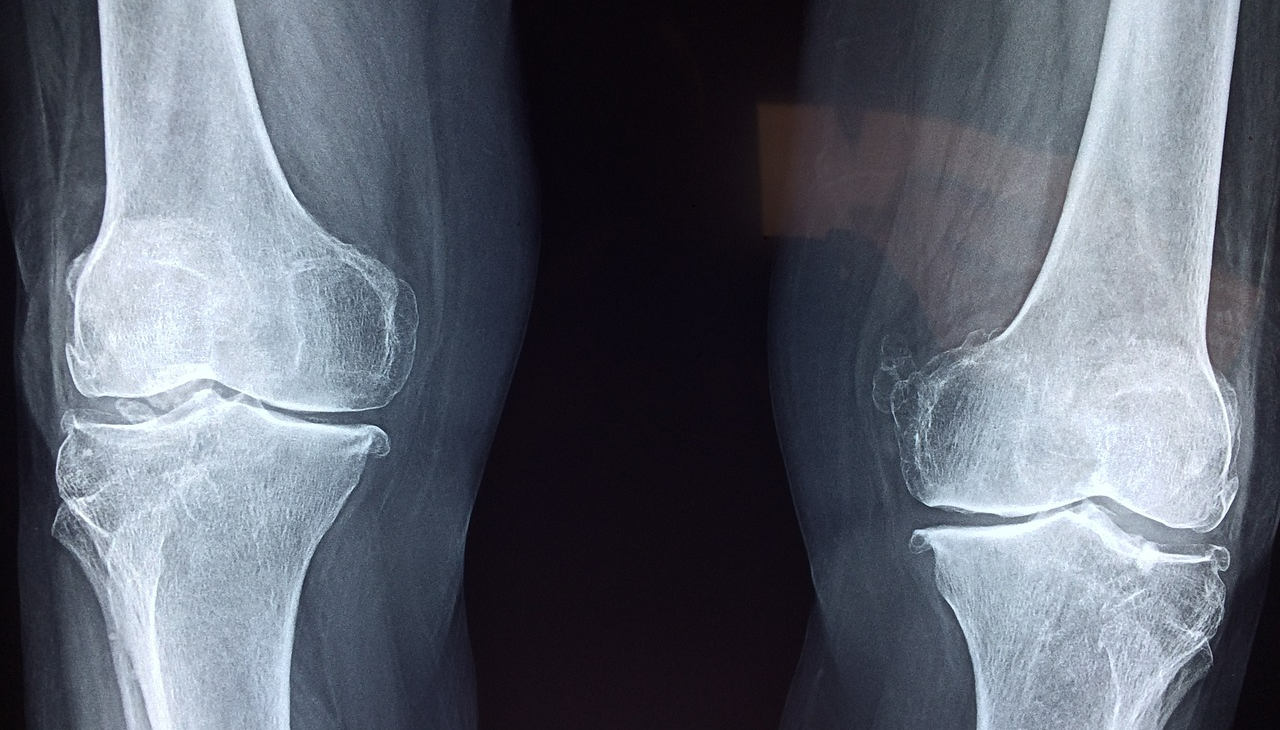

중년 여성들은 특히 폐경 이후 골다공증 위험이 급격히 증가합니다. 폐경이 되면 여성 호르몬인 에스트로겐 분비가 급격히 감소하게 되는데, 이 호르몬은 뼈를 보호하는 역할을 합니다. 에스트로겐 수치가 낮아지면 뼈의 밀도가 빠르게 감소하며, 이는 골다공증과 골절로 이어질 가능성을 높입니다. 골다공증은 초기에는 별다른 증상이 없기 때문에 "조용한 질병"이라고도 불립니다. 하지만, 시간이 지나면서 허리 통증, 척추 압박골절, 키 감소, 골절 등의 문제로 이어질 수 있습니다. 특히 중년 여성들은 바쁜 스케줄과 영양 불균형으로 인해 이런 위험 요소에 노출되기 쉽습니다. 이에 따라 골다공증을 예방하려면 올바른 생활 습관을 유지하고, 뼈 건강을 위한 필수 영양소를 적절히 섭취해야 합니다. 칼슘, 비타민 D, 그리고 마그네슘은 중년 여성의 뼈 건강에 특히 중요한 3대 필수 영양소로 알려져 있습니다. 이 영양소들을 일상적인 식단에 포함시키는 것이 골다공증 예방의 첫걸음입니다.

마지막으로, 정기적인 건강 검진을 통해 골밀도를 체크하세요. 골다공증은 조기에 발견할수록 치료가 수월하며, 예방적인 대처가 가능합니다. 특히 중년 여성이라면 골밀도 검사를 통해 자신의 뼈 건강 상태를 확인하고 적절한 조치를 취하는 것이 중요합니다.